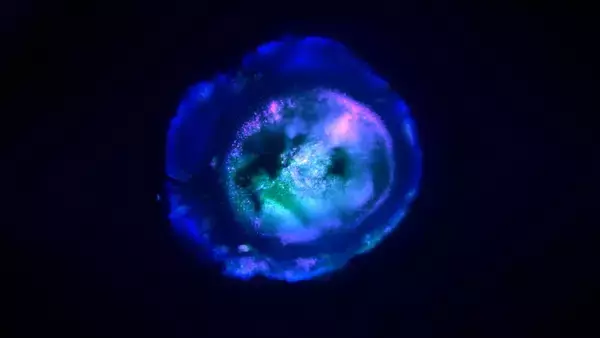

このたび、アメリカのジョンズ・ホプキンス大学の研究チームが開発した新たな脳オルガノイドは、神経組織だけでなく血管構造も備えており、複数の脳領域が接続された脳全体のモデルとして機能するという。

胎児の脳に似た神経活動も確認されており、人工的に再現された脳としてはこれまでにない構造を持つ。

この融合体は、「多領域脳オルガノイド(Multi-Region Brain Organoid:MRBO)」と名付けられている。

観察によれば、内部では異なる脳領域の神経細胞が連携して電気信号を発しており、約600万~700万個の神経細胞が含まれているという。

これは、胎児の脳が発達を始めた頃(約40日齢)に見られる構造と非常に似ており、脳全体のネットワークの縮図としては十分なモデルだ。

このオルガノイドの内部では、血管の成長も確認された。神経組織の間に血管網が自然に形成され、一部では新しい血管が枝分かれして発達する様子も観察されている。